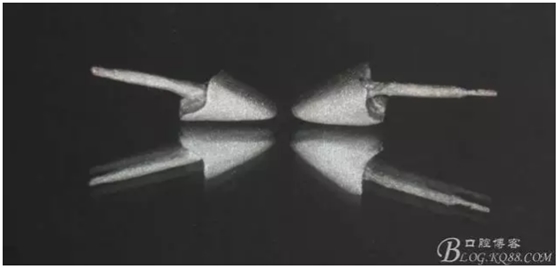

又囑咐病人半年復(fù)診一次,患者又過了兩年出現(xiàn)問題,再一次來到我們醫(yī)院,前牙咬螃蟹折斷了,我那個后悔啊,當(dāng)初要打了樁有多好,但是病人對我的信任,認(rèn)為咬硬物折斷是他的原因,只要給他修復(fù)上就好了

缺損太多 是必須用金屬樁修復(fù)的,

還要有足夠的牙本質(zhì)肩領(lǐng),大家現(xiàn)在可以看到患者的下頜套筒冠還是非常好的